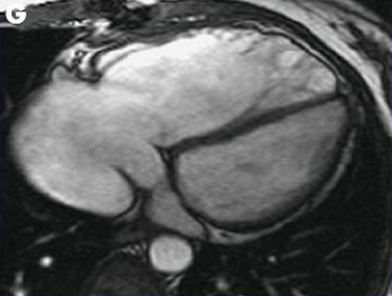

Ressonância nuclear magnética em um paciente com regurgitação pulmonar após reparo de tetralogia de Fallot. O paciente tem ventrículo direito restritivo e o coração é pequeno

De: Chaturvedi RR, Redington AN. Heart. 2007 Jul;93(7):880-9; usado com permissão